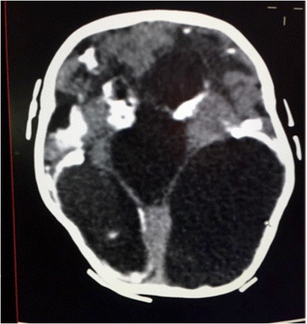

Hypertensive ventriculomegaly with gross parenchymal and basal ganglia calcifications